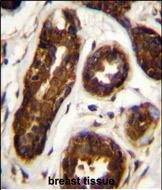

| IHC | 1/100-1/500 | Human,Mouse,Rat |

Maspin antibodies are essential tools for detecting maspin expression in research and diagnostics. Commonly used in techniques like immunohistochemistry (IHC), Western blotting, and immunofluorescence, these antibodies help correlate maspin levels with clinical outcomes. Studies associate maspin loss with poor prognosis in breast, prostate, and pancreatic cancers, though conflicting findings underscore the influence of tumor microenvironment and post-translational modifications. Commercially available maspin antibodies include monoclonal (e.g., mouse-derived clones G167-70 and EAW24) and polyclonal variants, often validated for specificity using knockout controls or peptide blocking assays. Challenges include cross-reactivity with other serpins and variability in formalin-fixed tissue staining. Beyond oncology, maspin antibodies aid studies in developmental biology and epithelial-mesenchymal transition (EMT), reflecting its role in cellular differentiation and tissue homeostasis. Ongoing research aims to clarify maspin's dualistic functions and therapeutic potential.